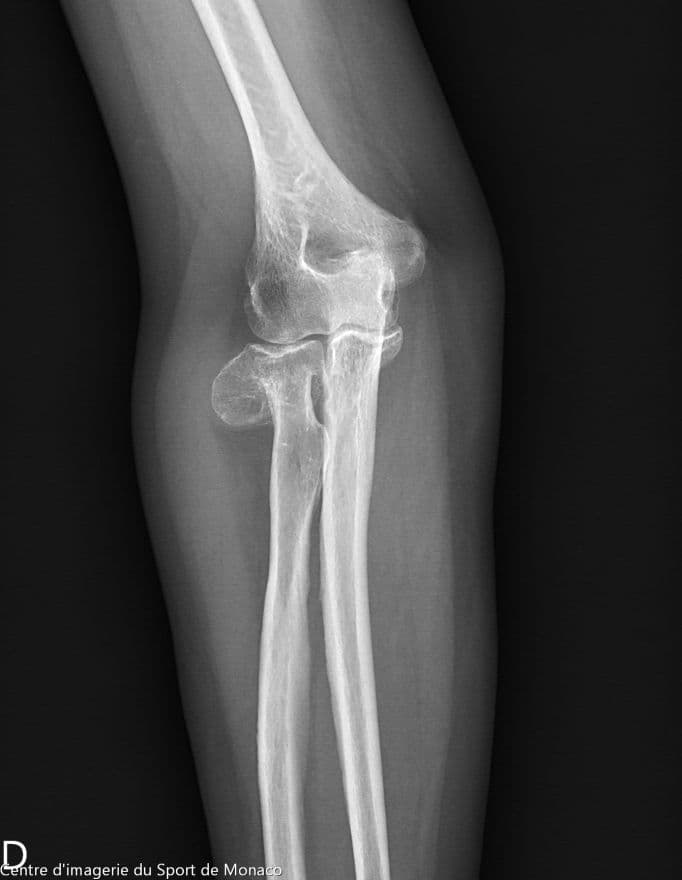

Radiographie

Excroissance osseuse au niveau métaphysoépiphysaire de la tête radiale qui évoque un ostéochondrome à large base d’implantation

Aspect post chirurgical de résection de la tête radiale.